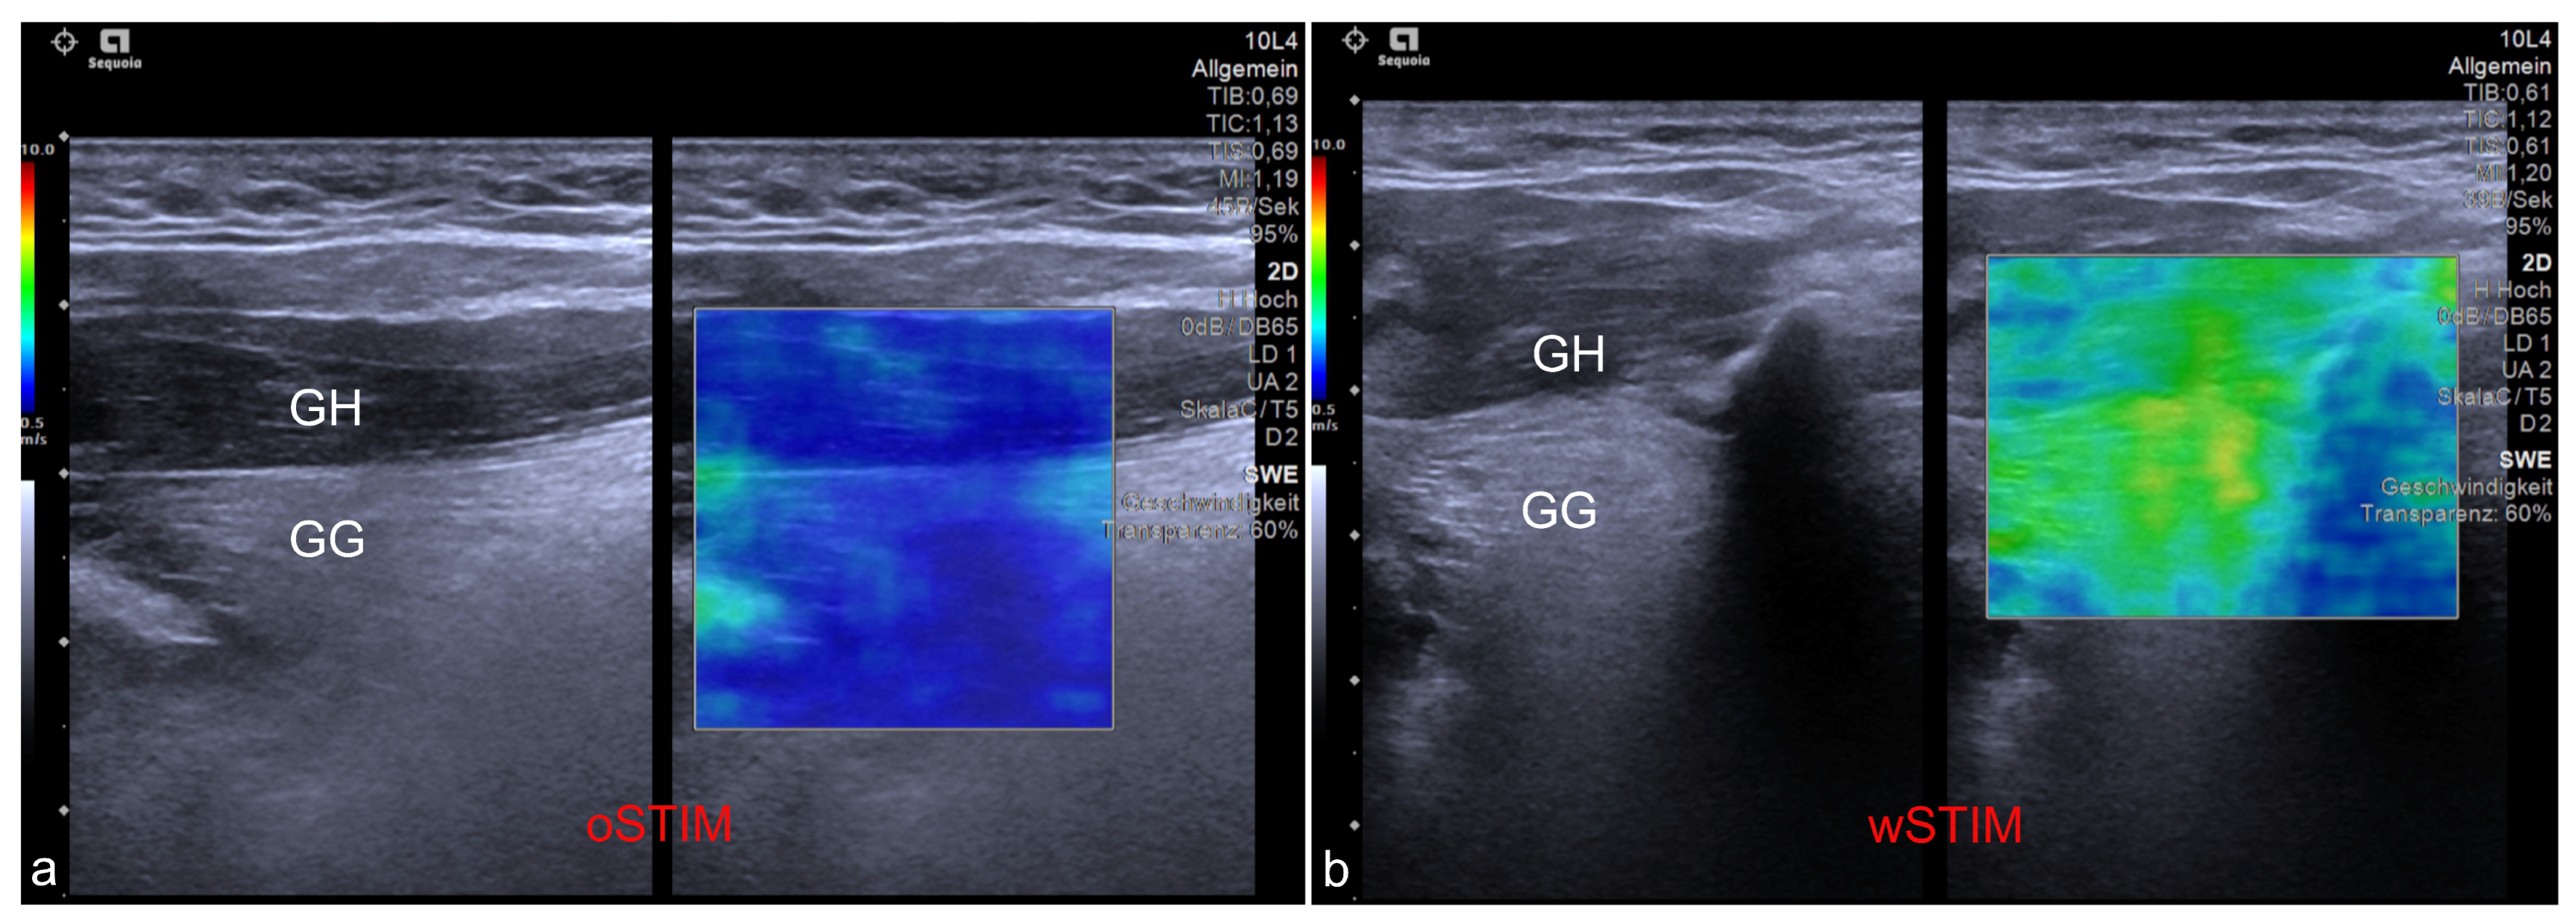

Figure 2.

Exemplary ultrasound images showing the application of shear wave elastography at the genioglossus (GG) and geniohyoid (GH) muscles. (a) Measurement of a patient without stimulation of the hypoglossal nerve (oSTIM). (b) Measurement of a patient during stimulation of the hypoglossal nerve (wSTIM).

A cohort of 18 out of 25 patients with an udHNS system (Inspire Medical Systems, Inc., Minneapolis, MN, USA) implanted an activated at our department between August and November 2020 that agreed to take part at the study. Median age was 62 years (IQR, 55–65). Thirteen patients were male (83.3%). Median body mass index (BMI) was 30.4 kg/m2 (IQR, 27.3–32.1). The US-SWE data were collected as follows and have been published in detail by Arens et al. 2021 [16] with a dedicated description of the technique. Patient position was supine with the head raised. First, gray-scale B-mode US of the tongue and submandibular area was performed in transverse and longitudinal planes for adequate assessment of target muscles. Examinations were performed using a high-end US system with a 4–10 MHz multifrequency linear array transducer and a center frequency of 7 Mhz (Acuson Sequoia, Siemens Healthineers, Erlangen, Germany). Quantitative evaluation of tissue stiffness was acquired by Virtual Touch™ software (Virtual Touch 2D SWE-Small Parts, Software Version VA11 using the ACUSON Sequoia, General software Version 1.0, Siemens Healthineers, Erlangen, Germany) allowing real-time measurement using acoustic radiation force impulse (ARFI) imaging technology. US-SWE examinations were performed in longitudinal to visualize superficial geniohyoid and deeper genioglossal muscles in one image (see also Figure 1 and Figure 2). Two-dimensional SWE approach was used to take repeated SWE measures before and during electrical stimulation with the predefined, patient-adapted parameters (amplitude, frequency, duration of stimulation). Representative stiffness indicated as SWE of each measured muscle without and with stimulation was given as the median of 15 measurements and corresponding interquartile range. Median SWV pre stimulation was 2.11 m/s (IQR, 1.92–2.49) for the sGH muscle and 2.50 m/s (IQR, 2.04–3.00) for the sGG muscle. SWV for the nGh muscle was 2.03 m/s (1.75–2.49) and 2.48 m/s (2.18–2.80) for the nGG muscle pre stimulation. Configuration settings of the stimulator were: “+-+” (bipolar) in 17 patients and “0-0” (unipolar) in one patient. Stimulation duration was 90 ms in 17/18 patients and 60 ms in 1/18 patients. The frequency of stimulation was 33 Hz in all patients. The SWV values of the patients under the individual therapeutic setting were as follows: median SWV in the sGH muscle was 2.53 (IQR, 2.20–3.69) m/s and in the sGG muscle 4.78 (IQR, 4.04–5.36) m/s. At the contralateral side SWV in the nGH muscle was 1.96 (IQR, 1.62–2.09) m/s and at the nGG muscle 2.21 (IQR, 1.73–2.39) m/s. The cohort show following tongue protrusion pattern during stimulation: protrusion to opposite site of stimulation n = 8/18 (44.4%), bilateral (symmetric) protrusion n = 9/18 (50.0%). One patient showed a tongue protrusion that did not match both patterns [4] (see also Figure 3). Within the scope of this study, the outcome of the udHNS therapy was assessed. The clinical sleep parameters of the patients (apnea, hypopnea index, and Epworth sleepiness scale (ESS)) were collected. If a current polysmonography (PSG) with the tested parameters was available, it was used for analysis. If not, a current PSG at the sleep laboratory or at least polygraphy (PG) (due to the COVID-19 pandemic) with the tested parameters was performed. This study was conducted in accordance with the Declaration of Helsinki and with the approval of the local ethics committee (EA1/263/19). With the clinical sleep parameters collected, we analyzed the extent to which outcome correlated with the measured SWV values of musculi GG and GH and the extent to which clinically relevant group differences could be identified between patients with different tongue protrusion patterns. Continuous variables were tested for normal distribution (Kolmogorov–Smirnov test). Because not all data were normally distributed, variables are reported as median and interquartile range (IQR). Group differences were tested with Mann–Whitney U-test; correlations were examined with Spearman’s rank correlation coefficient. A two-sided significance level of α < 0.05 was defined to indicate statistical significance (p). Due to multiple testing, corrected p-values using Bonferroni–Holm’s method are also provided in the tables (corr. p). All statistical analyses were performed using SPSS software (IBM Corp., released 2019. IBM SPSS Statistics for Windows, Version 26.0. Armonk, NY, USA: IBM Corp.).